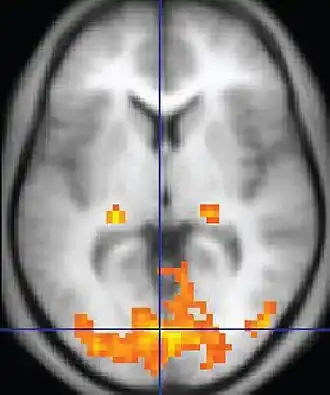

| Functional MRI (fMRI) | Blood-oxygen-level dependent imaging | BOLD | Changes in oxygen saturation-dependent magnetism of hemoglobin reflects tissue activity.[78] | Localizing brain activity from performing an assigned task (e.g. talking, moving fingers) before surgery, also used in research of cognition.[79] |

|